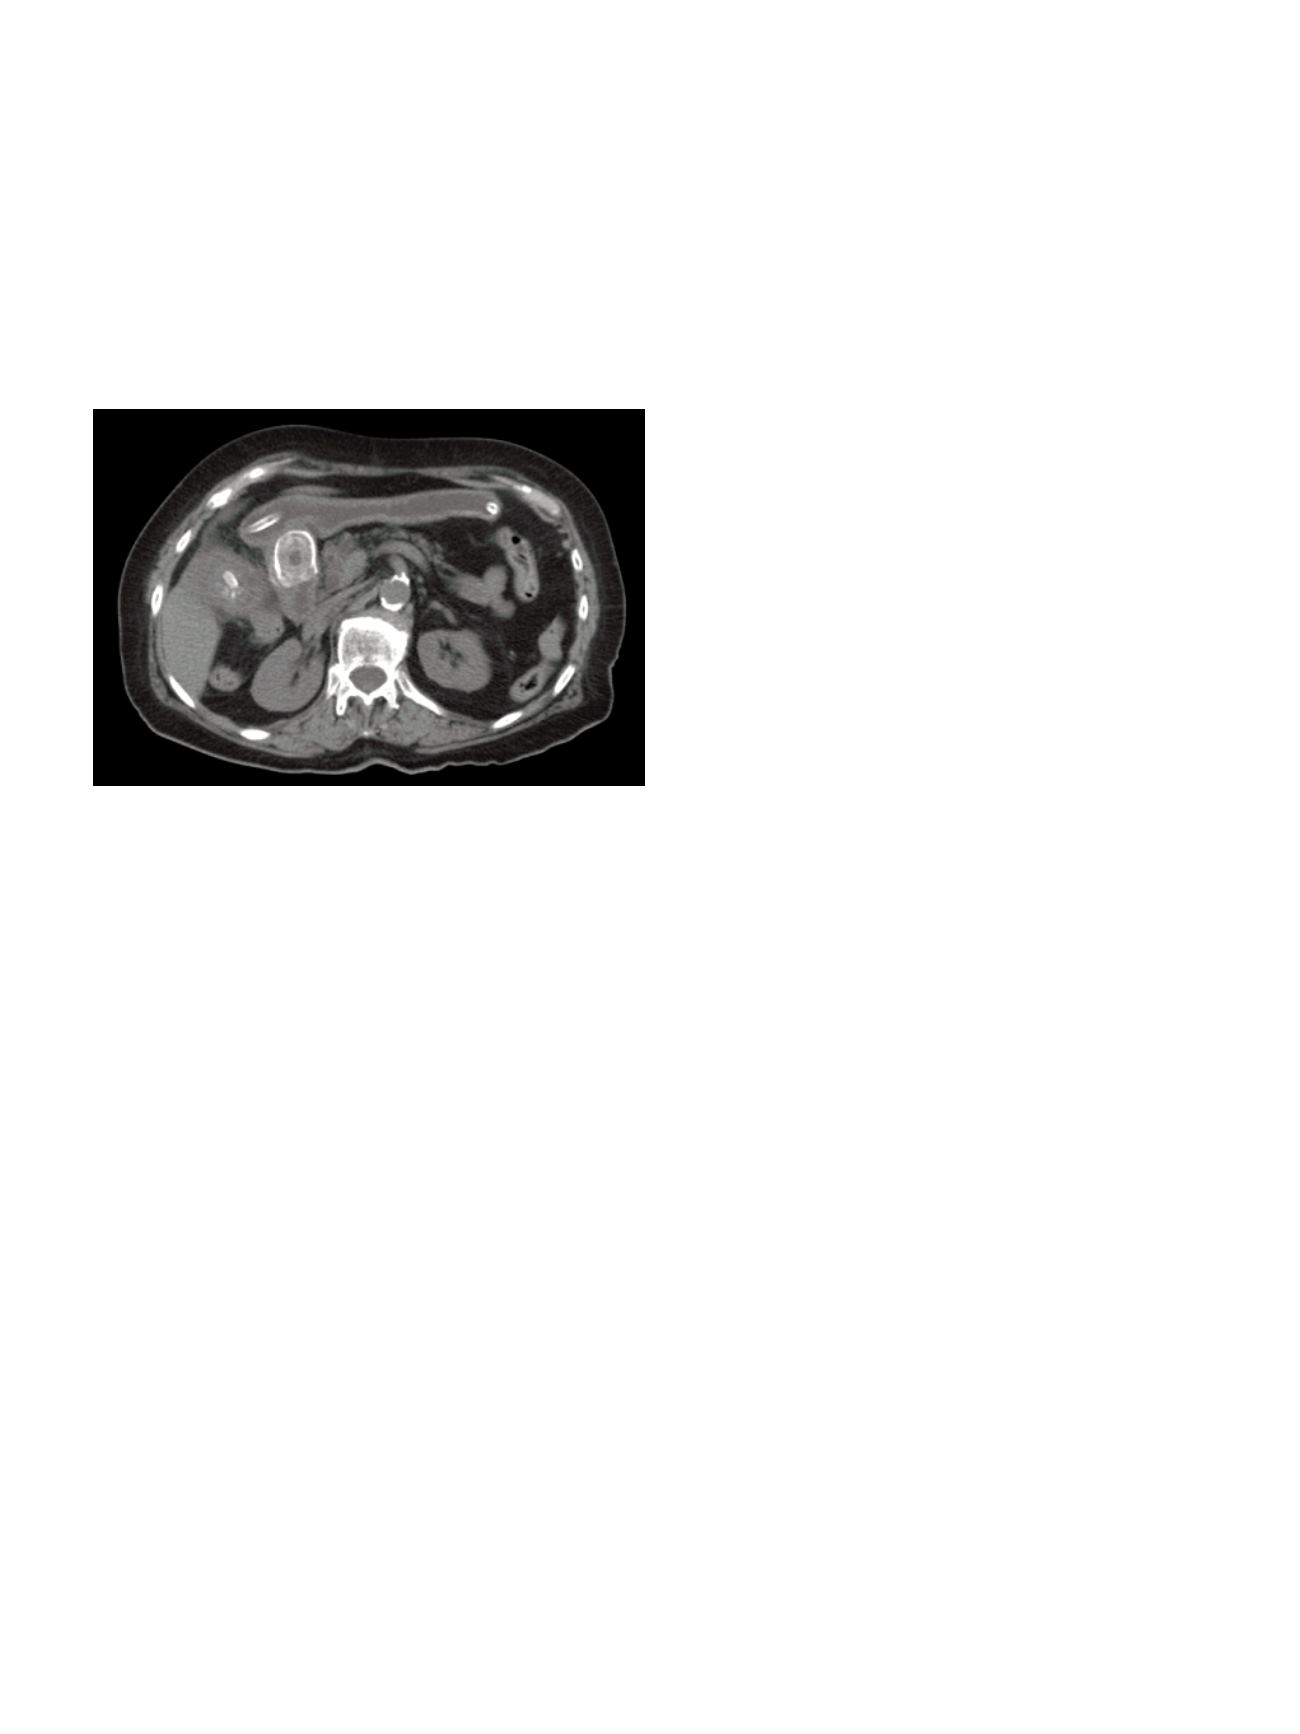

Case A: a 75-year-old woman presented with an incidentally

discovered, 4 cm cyst of the pancreatic body identified on CT scan.

Case B: a 45-year-old woman presented with a slightly growing 6

cm cyst of the pancreatic tail and two previous episodes of acute

pancreatitis. On EUS exploration contrast enhanced thin peripheral

septa were detected.